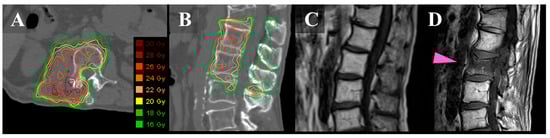

The SBRT technique has been discussed in great detail in previous publications [,] and is briefly summarized here. The clinical target volume included the gross tumor and the immediately adjacent bony anatomic compartments at risk of microscopic disease extension, as described by the contouring guidelines for spine SBRT [,]. A 2-mm margin was added to the clinical target volume to create the planning target volume (PTV). The prescribed dose (PD) was 20 Gy in a single fraction for curative intent, 24 Gy in two fractions for palliative intent, or 30 Gy in five fractions as a second SBRT course. The planning goal was that 95% of the PTV was irradiated by a dose (D95%) that was as close as possible to 100% of the PD under the condition that normal tissues satisfied the dose constraints (PTV D95% ≤ 100% PD). In addition, we set the following constraint for the PTV: the maximum dose should not exceed 140% of the PD (PTV Dmax ≤ 140% PD) between August 2013 and March 2019 (Figure 1A,B) and 160% of the PD (PTV Dmax ≤ 160% PD) between April 2019 and January 2020. From February 2020 onward, the maximum dose was set as lower than 170% of the PD (PTV Dmax ≤ 170% PD).

Figure 1.

Images of a 67-year-old man with metastatic L-1/2 sarcoma. Axial (A) and sagittal (B): CT images with dose distribution of SBRT. The spinal lesions show a right posterior involvement. (C): T1-weighted sagittal MRI before SBRT. (D): T1-weighted sagittal MRI 3 months after SBRT showing de novo VCF in the second lumber spine (pink arrow). The VCF did not cause pain. CT, computed tomography; MRI, magnetic resonance imaging; SBRT, stereotactic body radiotherapy; and VCF, vertebral compression fracture.

VCF events were defined as the development of a new VCF or the progression of an existing VCF in vertebral bodies, on the basis of imaging evaluations (Figure 1C,D) []. All post-SBRT images were reviewed to collect information on the incidence of VCF. First, the pathological VCF that was defined as a fracture with tumor recurrence before or at the time of developing into a VCF was excluded since the purpose of the current study was to assess the pain from VCF caused due to SBRT. The remaining iatrogenic VCFs were classified into three groups: painless (grade 1 according to Common Terminology Criteria for Adverse Events [CTCAE] version 5.0 []); mildly painful, needing prescription analgesics (grade 2); and intensely painful, requiring hospitalization or invasive interventions such as percutaneous cement injection or surgery (grade 3). If the patients had VCF at two spinal levels and pain in the area, we counted it as double-painful VCF.